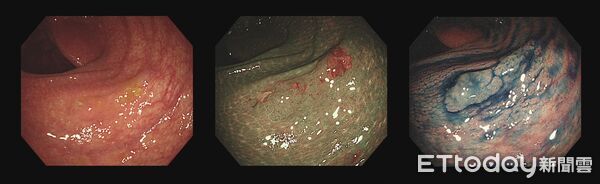

▲「大腸鋸齒狀腺瘤」邊緣不明顯難以診斷。(圖/葉人豪醫師授權提供,下同,未經同意請勿任意翻攝)

▲原始白光圖(左)息肉本身的範圍並不明顯,經切換影像模式(中)及用藍色染劑染色後(右)整個邊緣才變得清楚。

葉人豪指出,大腸鋸齒狀腺瘤型態特殊,外觀與邊緣都不明顯,是大腸鏡檢的「隱形殺手」。根據統計,近20年全世界對於大腸鋸齒狀腺瘤的平均偵測率低於5%,而義大大昌醫院團隊發表的論文,經由病理確認的鋸齒狀腺瘤偵測率超過6.5%,在在顯示其對醫師的專業、集中力和細緻度都有很高的要求。